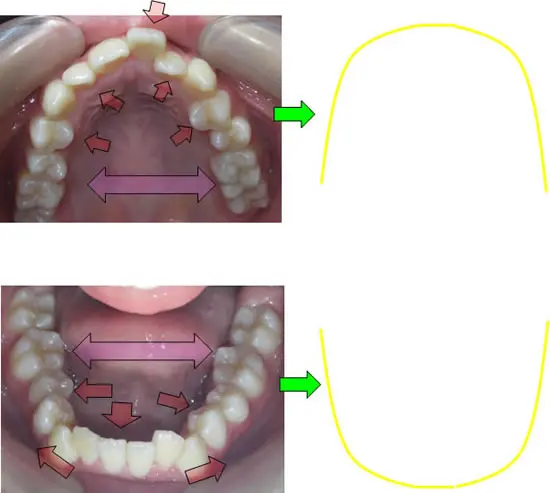

本来、この方が本来成長するはずであったところは上記のような上下顎のイメージになります!

顎が成長して(咀嚼や周囲の筋肉の調和などにより)歯が並ぶのに十分なスペースができさえすれば、乱れて生えてきた歯は自然に本来その歯が並ぶべき位置まで動いていってくれるという発想です

顎が小さいものは、歯を顎のサイズ合わせて歯を並べていく。歯を抜いて数を減らすことにより、スペースを作り並べていく。という発想が一般的な矯正治療の考え方です。

SH療法は本来成長するはずであったところまで誘導(成長)していくという発想です。歯を並べるのは、あなた方自身の生体で歯自身が居心地の良い場所へ動いていくという発想です。(また、装置を外している時間の方が長く、正しい咀嚼、姿勢などが大変重要になります)